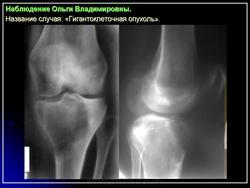

Обычно в пораженном метафизе располагается овальный очаг разрежения, кортикальный слой на его уровне истончен, кость «вздута». При небольшом распространении опухоль располагается несколько эксцентрично, а при обширном поражении — центрально.

При агрессивном течении процесса кортикальный слой истончается до толщины папиросной бумаги, а иногда разрушается. Остеопороз отсутствует. Структура очага крупноячеистая, а при литической форме однородно просветленная. Разрушения суставного хряща не наблюдается.

Рентгенологическое исследование гигантоклеточной опухоли показывает, что гигантоклеточиая опухоль локализуется в эпифизе и распространяется на метаэпифизарную часть кости. Поражение носит литический характер, имеет четкие контуры и умеренно или слабо контрастные костные балки. На границе метафиза контуры новообразования менее четкие, чем на остальном протяжении. Склеротические изменения вокруг опухоли развиваются редко, а такие угрожающие признаки, как козырек Кодмена или «лучистый венец», очень редки. Многие гигантоклеточные опухоли не выходят за пределы пораженной кости, но иногда они прорастают кортикальный слой и выходят в мягкие ткани, где покрываются тонким слоем новообразованной кости, едва заметкой при рентгенологическом исследовании. Такие же новообразования кости в виде «яичной скорлупы» имеются в имплантатах опухоли в мягких тканях и в метастазах в легких. Некоторые исследователи различают три стадии развития гигантоклеточной опухоли. На первой стадии узел небольшой, бессимптомный и не выходит за пределы пораженной кости. Вторая стадия документируется довольно объемным новообразованием, вплотную подходящим к наружному контуру кости. На третьей стадии опухоль проявляет агрессивные свойства и дает яркую клиническую симптоматику, связанную с се быстрым ростом и возникновением патологического перелома. На компьютерной томограмме отмечаются деструкция кортикального и медуллярного слоев и проникновение опухоли в окружающие мягкие ткани.